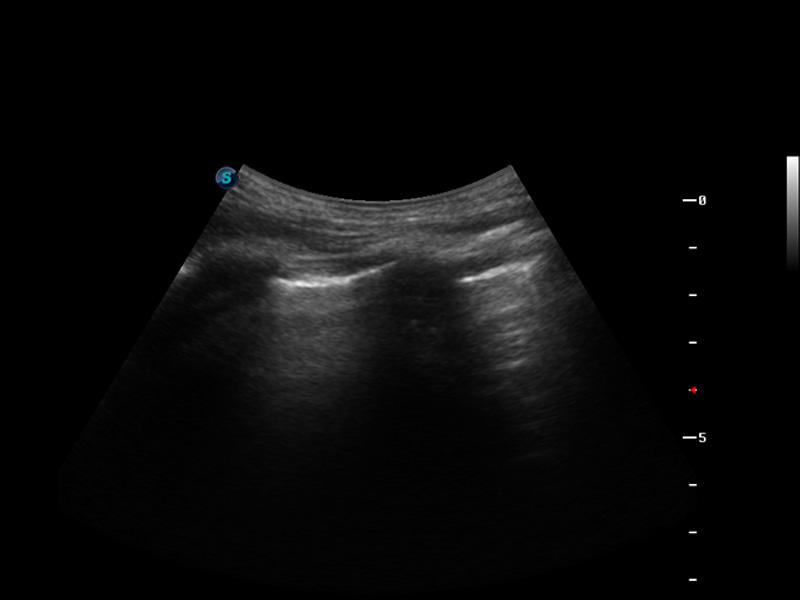

S9便携式彩色多普勒超声诊断仪是公海贵宾会员检测中心医疗研发的高端便携彩超设备,外观设计新颖、产品性能卓越。S9在便携超声领域采用了突破传统的触摸屏交互设计,并以先进的软件硬件技术和设计理念,为您带来清晰的图像质量、稳定的工作性能和便捷的操作体验。

成像技术